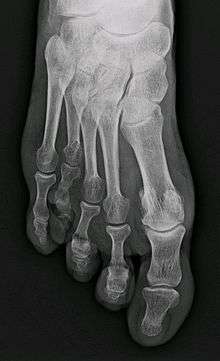

Brachymetatarsia or hypoplastic metatarsal is a condition in which there is one or more abnormally short or overlapping toes metatarsals.[1] This condition may result due to a congenital defect or it may be an acquired condition.[1] It most frequently involves the fourth metatarsal. If it involves the first metatarsal, the condition is known as Morton's syndrome.[1] Treatment is via a number of differing surgical procedures.[1]